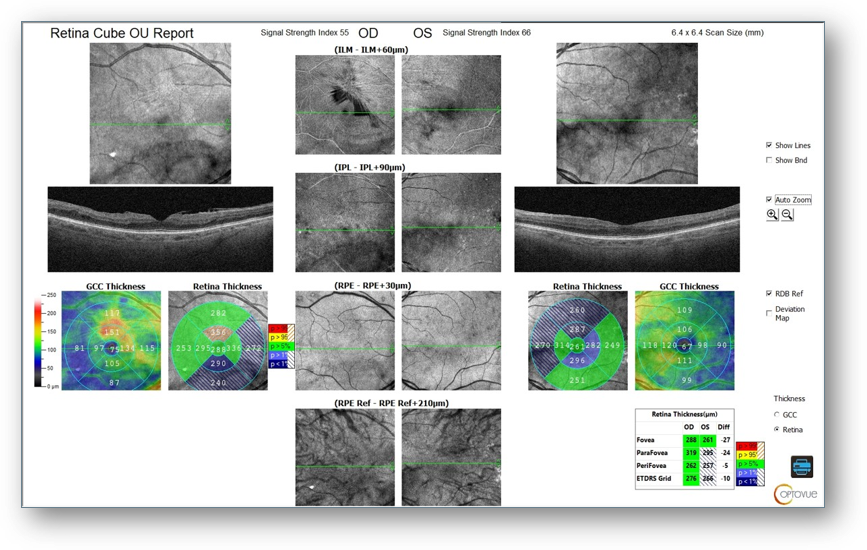

Fundus images showed small hard drusen throughout both maculae but no diabetic retinopathy (Figure 6). OCT revealed small drusen OU, mild ERM OD, and no diabetic retinopathy or macular edema (Figure 7). Notably, abnormal and asymmetric FAZ and capillary dropout OD > OS were found on OCT-A (Figure 8). These structural findings, combined with the patient’s poorly controlled diabetes secondary to medication unavailability were cause for concern and prompted me to perform ERG.

Figure 7: OCT

Figure 8: OCT-A